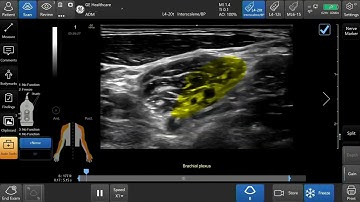

Venue Family Tutorials: Optimizing Color PDI